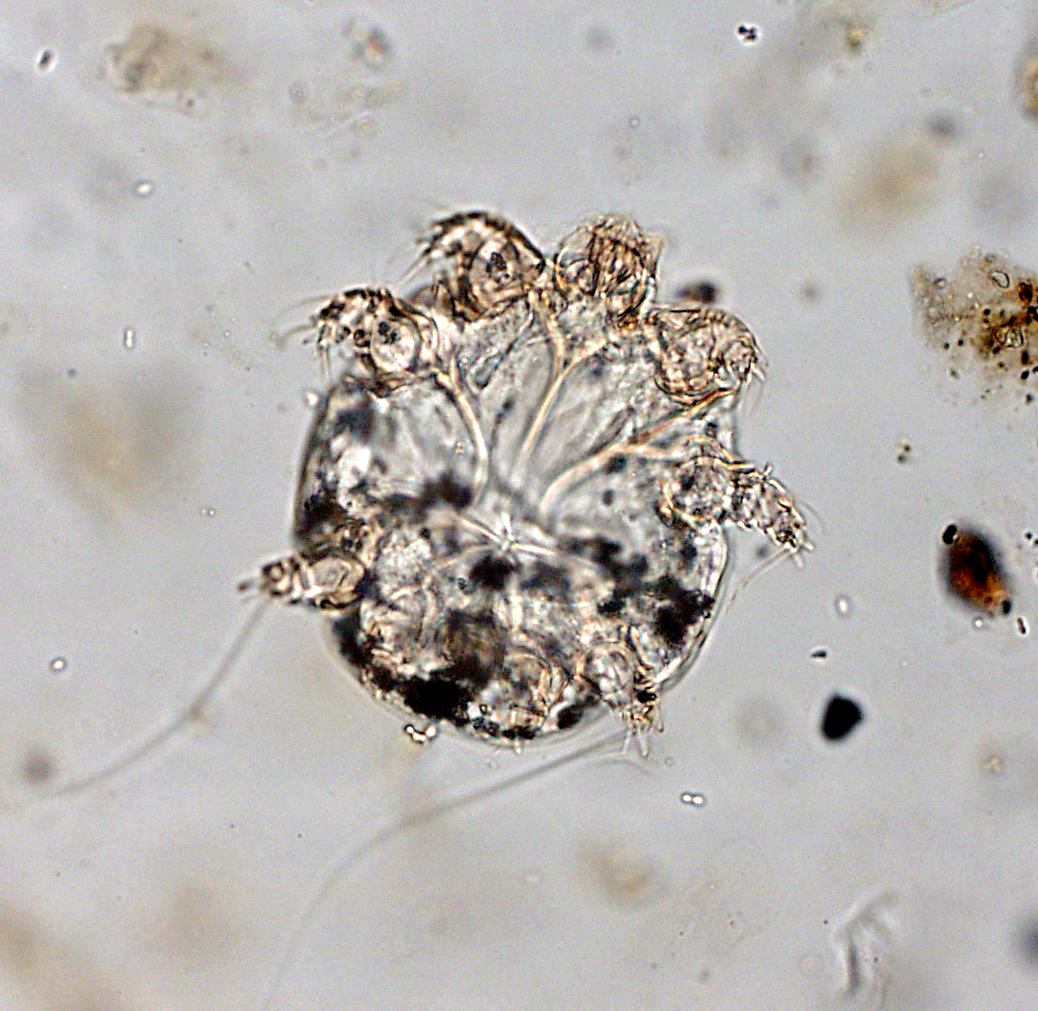

При подозрении на нотоэдроз ветеринарный врач берет соскоб кожи с пораженных мест животного и отправляет в лабораторию для исследования под микроскопом и установления окончательного диагноза.